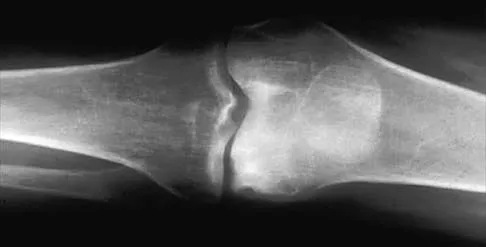

A 16-year-old girl has had pain in the left groin for the past 4 months. She notes that the pain is worse at night; however, she denies any history of trauma and has no constitutional symptoms. There is no history of steroid or alcohol use. Examination reveals pain in the left groin with rotation of the hip. There is no associated soft-tissue mass. A radiograph and MRI scan are shown in Figures 32a and 32b, and biopsy specimens are shown in Figures 32c and 32d. What is the most likely diagnosis?

Explanation